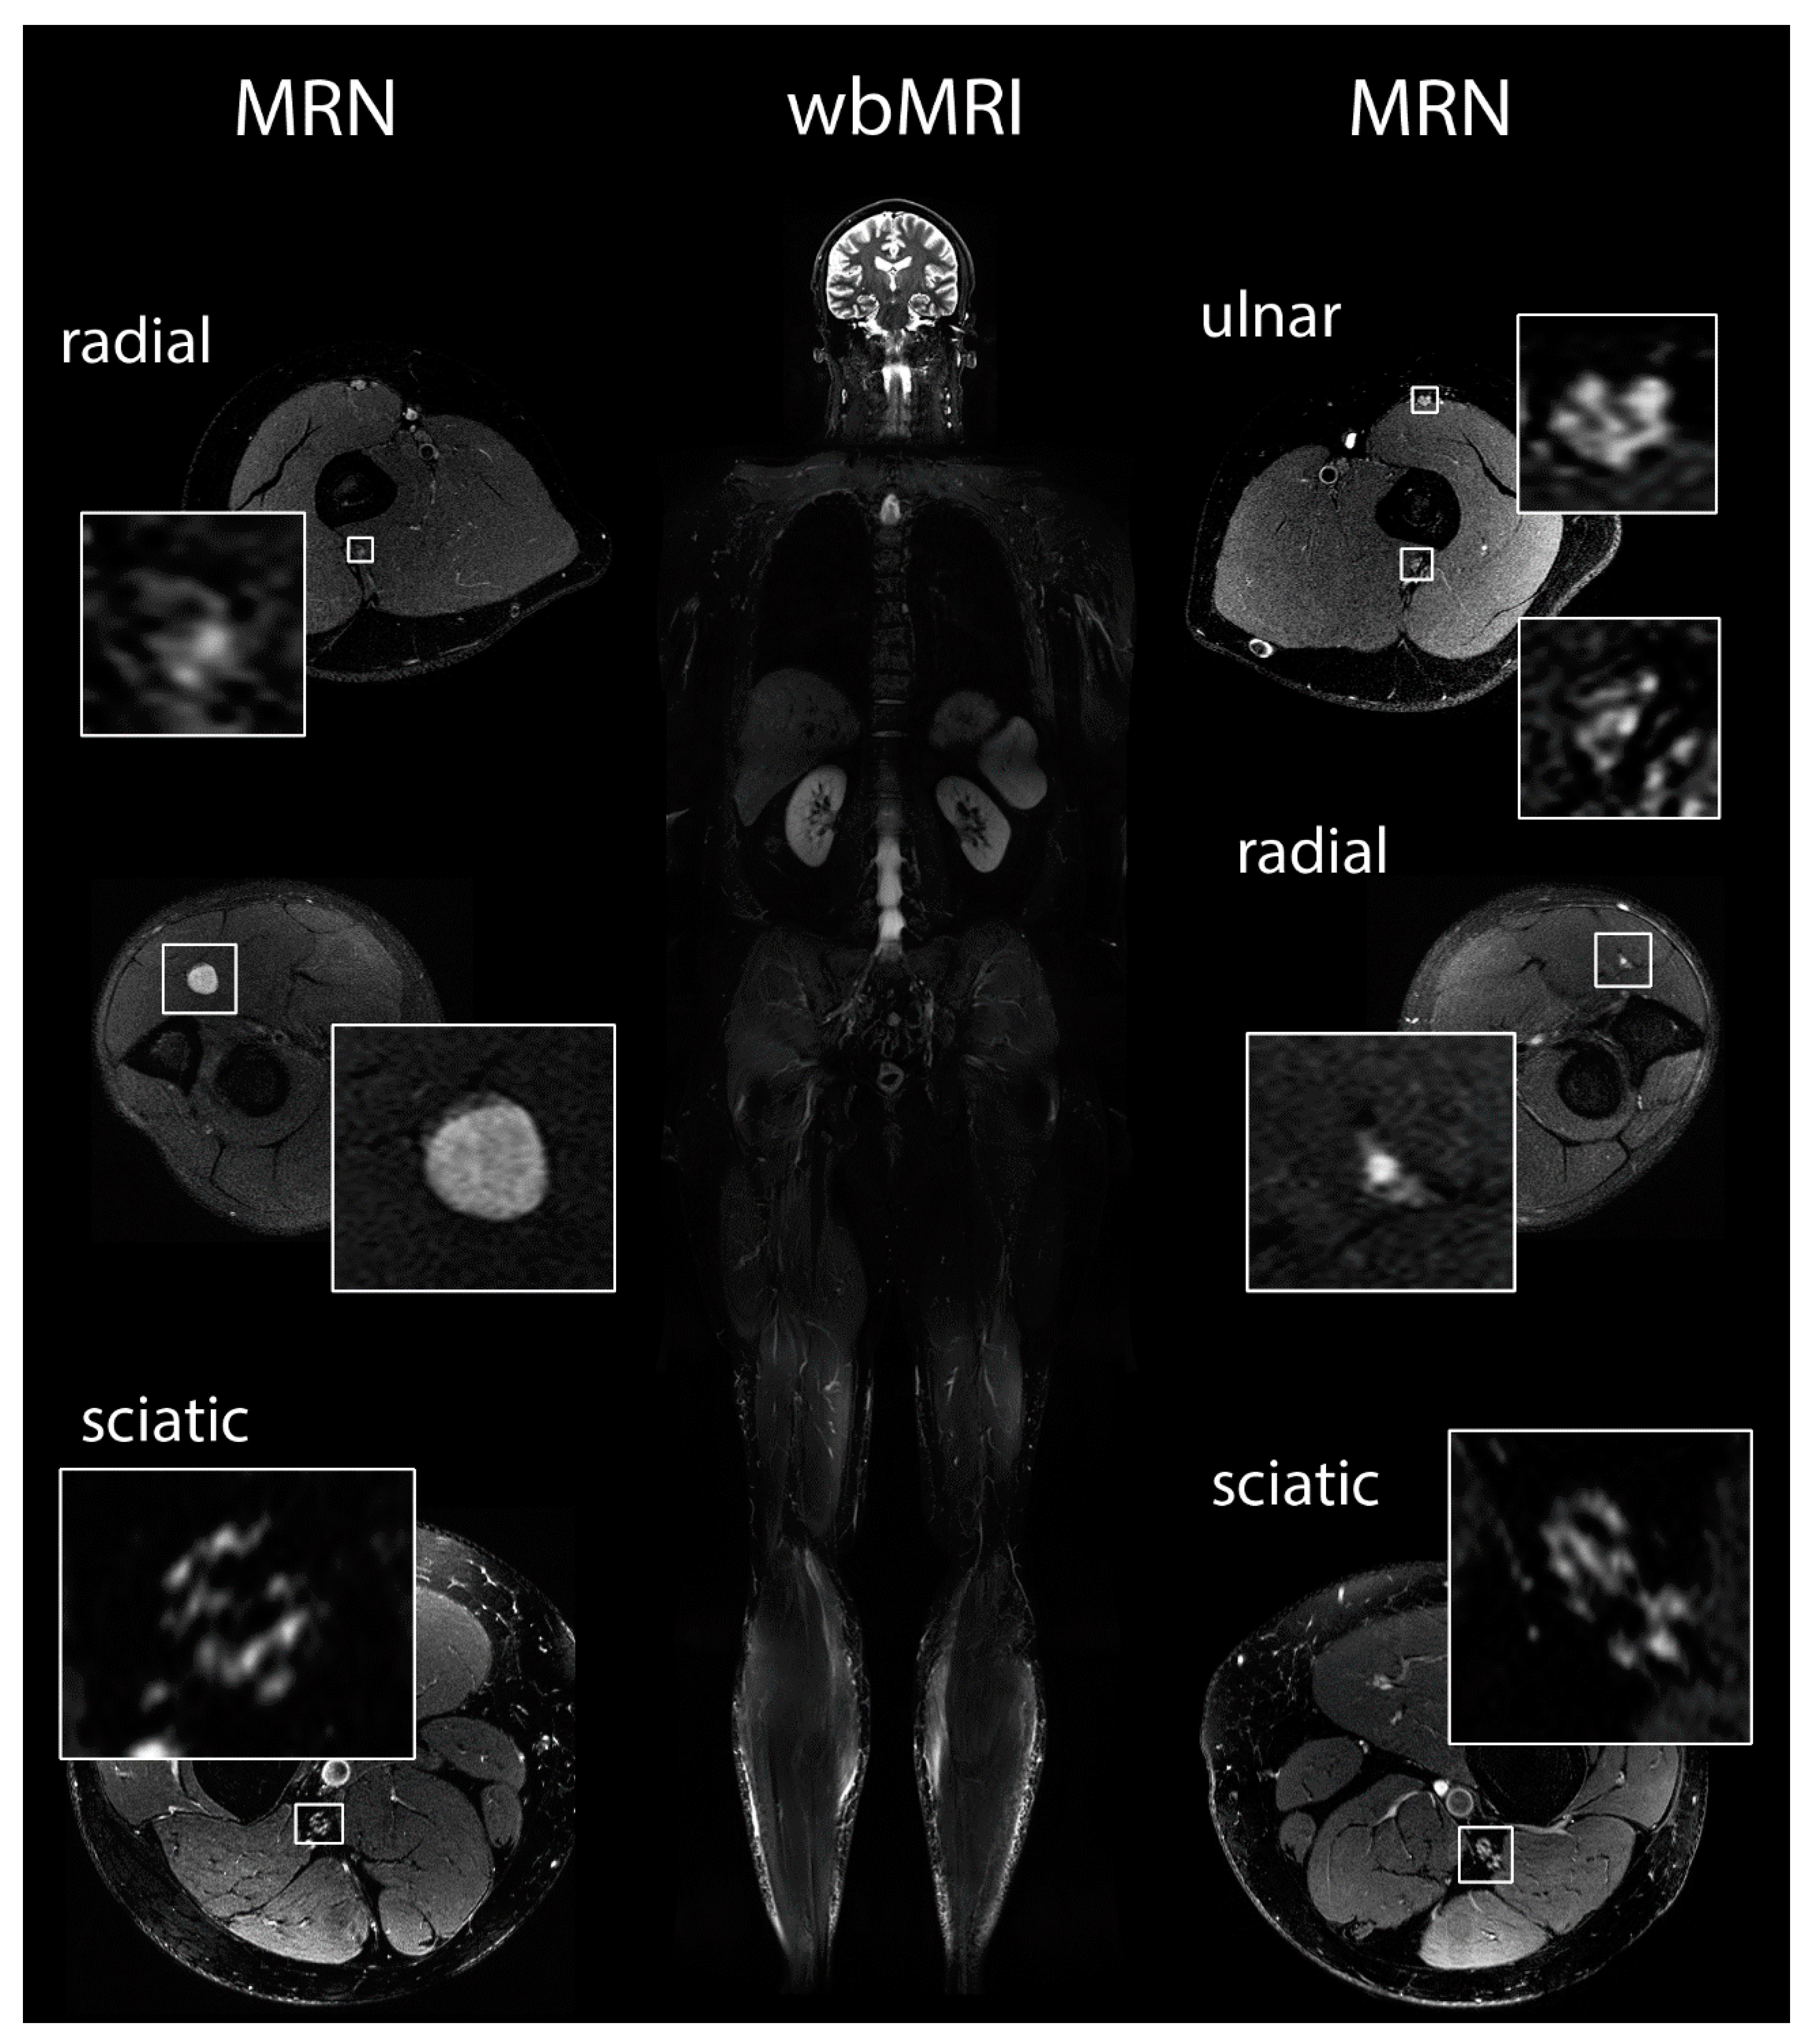

2.5. Magnetic Resonance Imaging and Magnetic Resonance Neurography

3.6. Magnetic Resonance Imaging and Neurography

- Farschtschi, S.; Mautner, V.-F.; Pham, M.; Nguyen, R.; Kehrer-Sawatzki, H.; Hutter, S.; Friedrich, R.E.; Schulz, A.; Morrison, H.; Jones, D.T.W.; et al. Multifocal nerve lesions and LZTR1 germline mutations in segmental schwannomatosis. Ann. Neurol. 2016, 80, 625–628. [Google Scholar] [CrossRef] [PubMed]